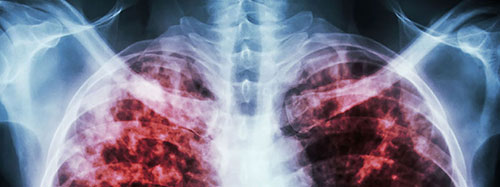

Le projet Help Stop TB a été créé pour étudier la gaine de Mycobacterium tuberculosis , la bactérie responsable de la maladie. Ces connaissances pourraient aider les scientifiques à mieux comprendre comment la bactérie se protège, ce qui pourrait à son tour aider à la recherche de meilleurs traitements.

En octobre, l'Organisation mondiale de la santé a publié les statistiques mondiales les plus récentes sur la tuberculose, notamment les suivantes :

- En 2019, environ 10 millions de personnes ont contracté la tuberculose.

- 1,4 million de personnes sont décédées de la tuberculose en 2019.

- La tuberculose reste l'une des 10 principales causes de décès dans le monde et la principale cause d'un seul agent infectieux (au-dessus du VIH / SIDA).